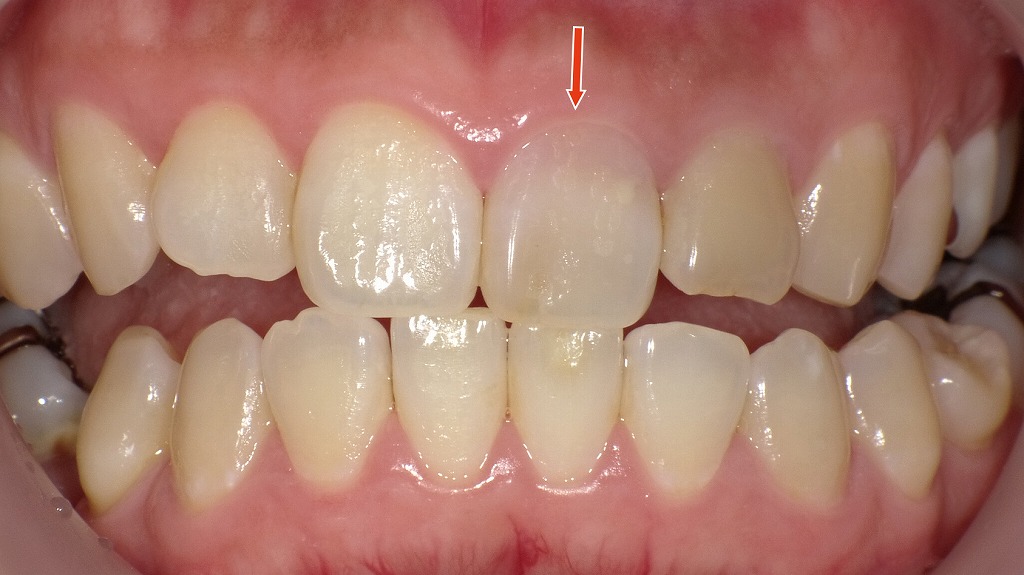

◆ホワイトニング前の口腔内写真

このの写真では、神経を失った前歯が周囲の天然歯よりも暗く、やや黄褐色が強い状態であることがわかります。これは、歯の内部(象牙質)が時間とともに変色し、その色が外側のエナメル質を通して透けて見えるためです。外側からのホワイトニングを行う前は、このように周囲の歯と色の差が大きく、単独で目立ちやすいのが失活歯の特徴です。